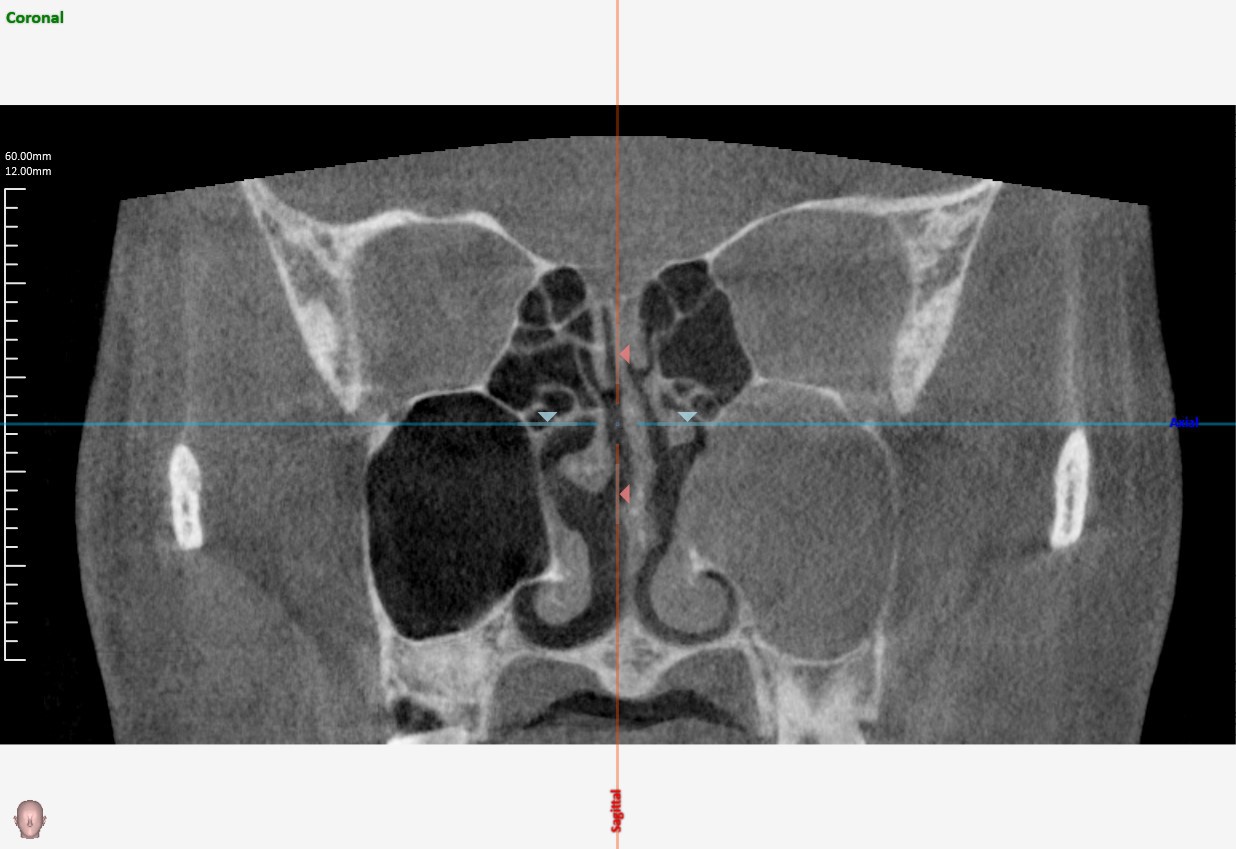

副鼻腔CT

- 特殊な副鼻腔炎(う歯による副鼻腔炎、真菌による副鼻腔炎)を疑う場合

- 副鼻腔の腫瘍を疑う場合

- レントゲンで病変がはっきりしない場合 など